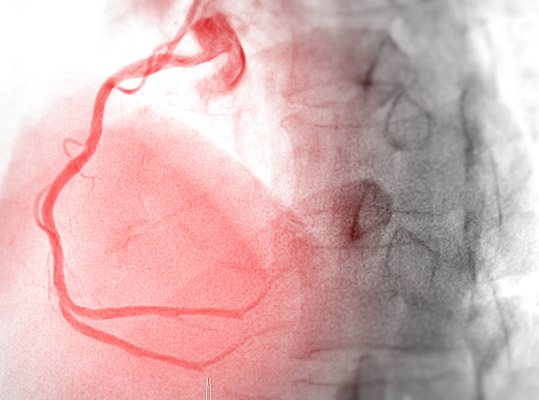

With a cardia stress test, our team can better understand and identify any issues in your heart. This test helps to measure what the heart goes through when under increased stress or stimulation. It is also sometimes referred to as an exercise test or treadmill test. A cardiac stress test involves inducing external stress on the heart through a controlled scenario of exercise to measure the heart's response.

A stress test monitors your heart’s response to increased stimuli and shows the changes that occur in your heart's activity. The doctor can see signs if there is not enough blood flowing to your heart during exercise. The stress test can also help determine whether your heart muscles are moving correctly. In addition, the test can show whether the heart valves are compromised and not opening or closing the way they should be.